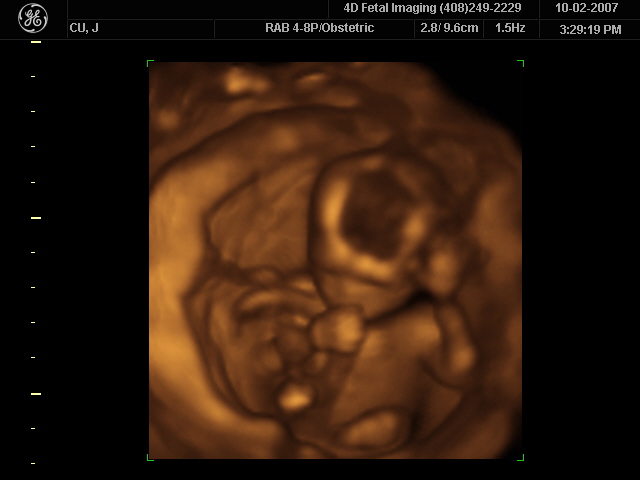

How much detail can ultrasound reveal? The image in Figure 17.45 is typical of low-cost systems, but that in Figure 17.46 shows the remarkable detail possible with more advanced systems, including 3D imaging. Ultrasound today is commonly used in prenatal care. Such imaging can be used

to see if the fetus is developing at a normal rate, and help in the determination of serious problems early in the pregnancy. Ultrasound is also in wide

use to image the chambers of the heart and the flow of blood within the beating heart, using the Doppler effect (echocardiology).

Figure 17.46 A 3D ultrasound image of a fetus. As well as for the detection of any abnormalities, such scans have also been shown to be useful for strengthening the

emotional bonding between parents and their unborn child. (credit: Jennie Cu, Wikimedia Commons)